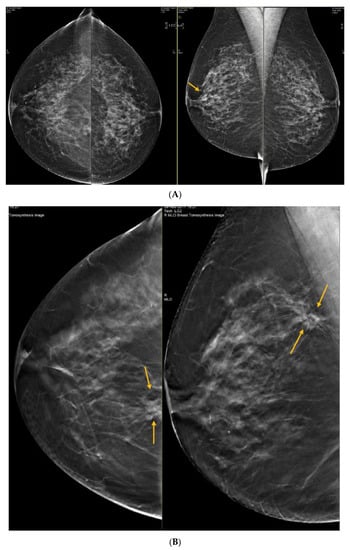

6. Digital Breast Tomosynthesis (DBT)